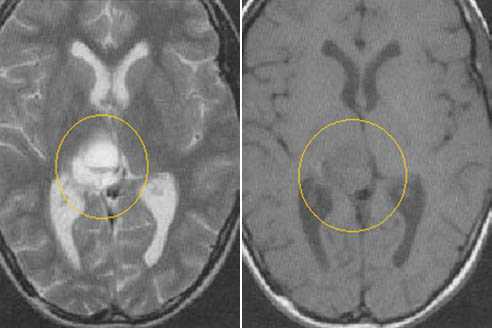

Пиллоидная астроцитома задних отделов III желудочка. Определяется небольших размеров образование с развитием окклюзионной гидроцефалии. Опухоль практически не отличается по сигналам от вещества головного мозга. После в/в контрастирование отмечается усиление МР-сигнала от образование, что позволяет уточнить расположение опухоли, степень компрессии четверохолмной пластинки и водопровода мозга.

Глиобластома зрительного бугра справа. До и после в/в контрастирования определяется объемное образование с некротическим центром и контрастируемой периферической инфильтративной частью. Деформированы задние отделы III желудочка, начальный проявления окклюзионной гидроцефалии.

Эпендимома задних отделов III желудочка. Определяется объемное образование в задних отделах шишковидной железы. Передние бугорки четверохолмия оттеснены вниз. Водопровод мозга сдавлен.